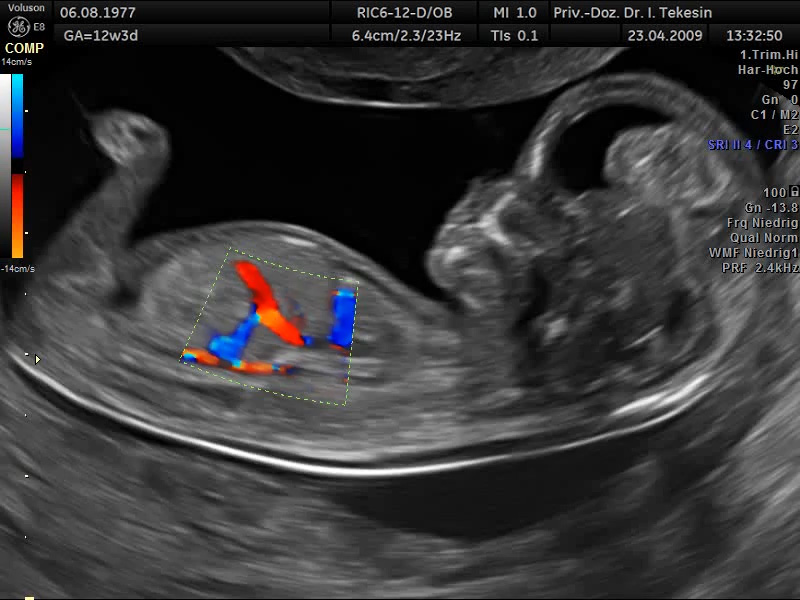

Fetale Zirkulation in der 13. SSW

Darstellung des DV in der 13. SSW mittels Farb-Doppler